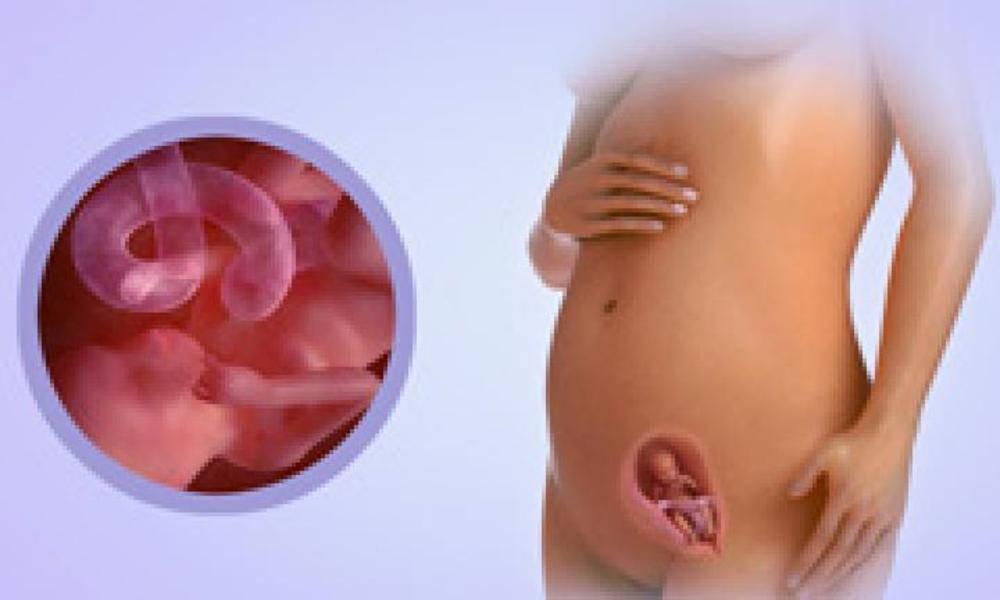

Важный этап: развитие малыша на 20-й неделе беременности